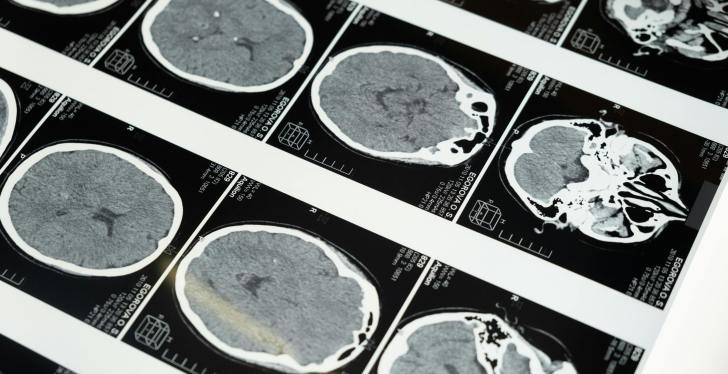

The parasite infects neurons in the brain and prevents them from producing as many extracellular vesicles. These are key in exchanging information, and so when affected, they can cause various issues in cognitive function.

The parasite can lie dormant in the brain for years and reactivate when the immune system becomes weakened or compromised. The effects can be serious, ranging from seizures to neural damage and altered brain connectivity.